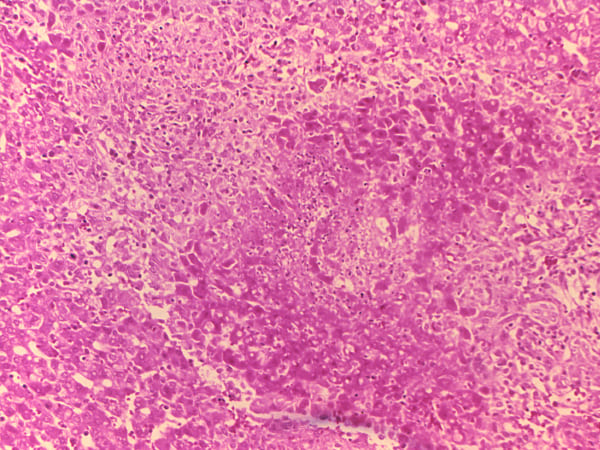

മൃഗങ്ങള്ക്ക് ബ്രൂസെല്ലോസിസ് വാക്സിനുകള് നിര്മ്മിക്കുന്ന ബയോളജിക്കല് ഫാര്മസ്യൂട്ടിക്കല് ഫാക്ടറി കഴിഞ്ഞ വേനല്ക്കാലത്ത് കാലഹരണപ്പെട്ട സാനിറ്റൈസറുകളുടെയും അണുനാശിനികളുടെയും ഉപയോഗം കാരണം ബ്രസെല്ലയുടെ (ബ്രൂസെല്ലോസിസിന് കാരണമാകുന്ന ബാക്ടീരിയ) എയറോസോളൈസ്ഡ് പതിപ്പ് വായുവിലേക്ക് കടന്നതായി അധികൃതര് കണ്ടെത്തി. ഇത് ചുറ്റുമുള്ള പ്രദേശത്തേക്ക് വായുവിലൂടെ ബാക്ടീരിയ രോഗം പടരാന് കാരണമായി. കരള്, പ്ലീഹ എന്നിവയുടെ വീക്കം, ശ്വാസകോശ സംബന്ധമായ പ്രശ്നങ്ങള്, പുരുഷന്മാരില് വന്ധ്യതയ്ക്ക് കാരണമാകുന്ന പ്രത്യുത്പാദന പ്രശ്നങ്ങള് എന്നിവ ഉള്പ്പെടെയുള്ള ഗുരുതരമായ പാര്ശ്വഫലങ്ങള് ഈ രോഗം മൂലം ഉണ്ടാവാം എന്ന് പ്രാധമിക നിരീക്ഷണത്തില് കണ്ടെത്തിയിട്ടുണ്ട്.

ബ്രൂസെല്ലോസിസ് രോഗത്തിന്റെ സങ്കീര്ണതകള് വളരെയധികം ശ്രദ്ധിക്കേണ്ടതാണ്. രോഗബാധയുണ്ടായി എന്ന് നിങ്ങള്ക്ക് തോന്നിയാല് അത് നിങ്ങളില് ഇനി പറയുന്ന പ്രശ്നങ്ങളാണ് ഉണ്ടാക്കുന്നത്. ഹൃദയം, കരള്, കേന്ദ്ര നാഡീവ്യൂഹം, പ്രത്യുല്പാദന സംവിധാനം എന്നിങ്ങനെ ശരീരത്തിന്റെ മിക്കവാറും എല്ലാ ഭാഗങ്ങളെയും അണുബാധ ബാധിച്ചേക്കാം. രോഗം മൂലമുണ്ടാകുന്ന ഗുരുതരമായ സങ്കീര്ണതകളിലൊന്നാണ് കോശജ്വലനത്തിന് കാരണമാകുന്നതെന്ന് പുരുഷന്മാരില് വന്ധ്യതയ്ക്ക് കാരണമാകുമെന്ന് ആരോഗ്യ വിദഗ്ധര് പറഞ്ഞു.